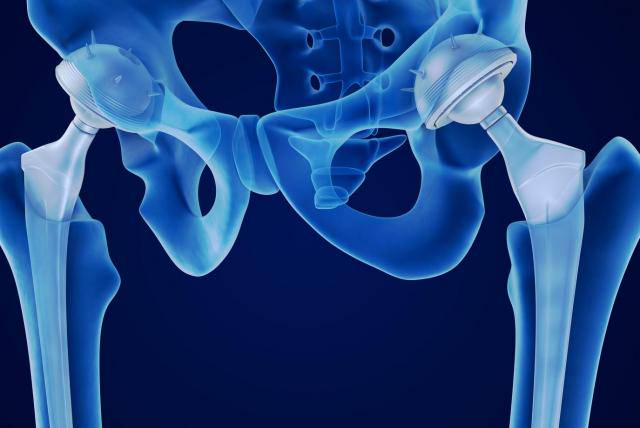

Reemplazo de cadera robótico de precisión submilimétrica: el nuevo estándar en recuperación y calidad de vida

La cirugía robótica permite una planificación personalizada y una ejecución con exactitud submilimétrica, mejorando la estabilidad, la seguridad y la recuperación funcional